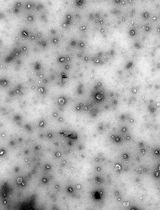

AFM images show that the Dil-labeled PLGA/PLA-PEG-FA nanoparticles are nano-sized particles with a spherical shape (Figure 5b).

Figure 5. Size, zeta potential, and morphology analysis of the nanoparticles. a) Size distribution of the nanoparticles; b) An AFM photo of the nanoparticle c) zeta potential of the nanoparticle. Different colored lines represent 3 readings of the same preparation.